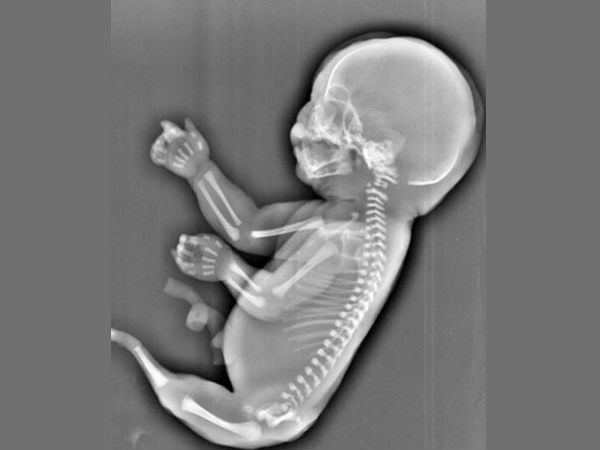

கருவில் வளரும் குழந்தை ஆணா, பெண்ணா என்று கண்டறிய உதவும் வித்தியாச தகவல்கள்!

குழந்தைகள் உருவாவது மிக அழகான அதிசயம்; கருவில் வளரும் குழந்தை ஆணா, பெண்ணா என்று கண்டறிய உதவும் வித்தியாச தகவல்கள் பற்றி இந்த பதிப்பில் படித்து அறியலாம்.

குழந்தைகள் உருவாவது மிக அழகான அதிசயம்; குழந்தைகள் பெண்ணின் வயிற்றில் உருவாக்கி வளர்வது எத்தகைய அதிசயம் என்பதை அதை வாழ்க்கையில் உணர்ந்து பார்க்கும் தம்பதியருக்கு மட்டும் தான் புரியும். குழந்தைகள் கருவில் உருவாகும் பொழுது கர்ப்பிணி எத்தகு சந்தோஷம் அடைகிறாளோ, அதே அளவு சந்தேகமாக, ஆர்வமாக அவள் மனதில் ஒரு கேள்வி எழும். அது தான் பிறக்கப்போவது ஆண் குழந்தையா? பெண் குழந்தையா? என்னும் கேள்வி.

இந்த கேள்விக்கான விடையை, அதாவது பிறக்க கருவில் வளர்ந்து பிறக்க போகும் குழந்தை ஆணா, பெண்ணா என்று கண்டறிய உதவும் வித்தியாச தகவல்கள் பற்றி இந்த பதிப்பில் படித்து அறியலாம்.